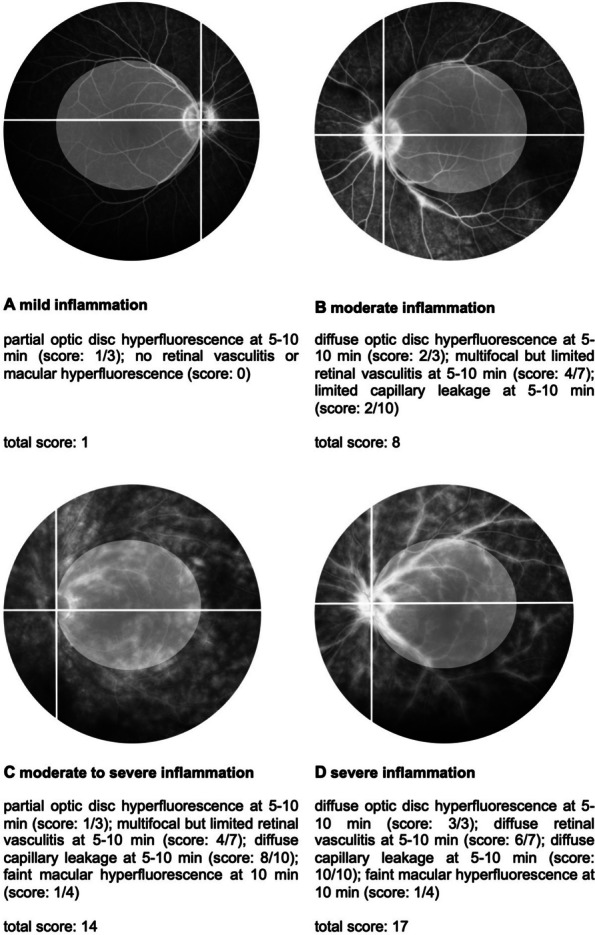

Methods: Eight patients (16 eyes) received TCZ and were included in the analysis. The primary outcomes measured were inflammatory activity in the retina and choroid, assessed by fluorescein angiography (FA) and indocyanine green angiography (ICGA) using the Angiography Scoring for Uveitis Working Group at baseline, 6, 12, 24, and 36 months.

Results: The mean follow-up time with TCZ treatment was 33 months. At baseline, the median FA score was 14 (quartiles: 10.25, 15.25), which significantly decreased over time (at 36 months: 8 (5.5, 11); p = 0.004). In contrast, the ICGA score significantly increased within the first year (median at baseline: 5 (4.75, 7.25); at 6 months: 7 (6, 9.25); at 12 months: 7 (6.5, 9.25); p = 0.002), but returned to baseline levels after two years (at 24 months: 5 (5, 6.5); at 36 months: 5.5 (4, 7.5)). Central retinal thickness (CRT) improved significantly after 6 months (median at baseline: 295 µm (275, 322); at 6 months: 275 µm (251, 308); p = 0.01).